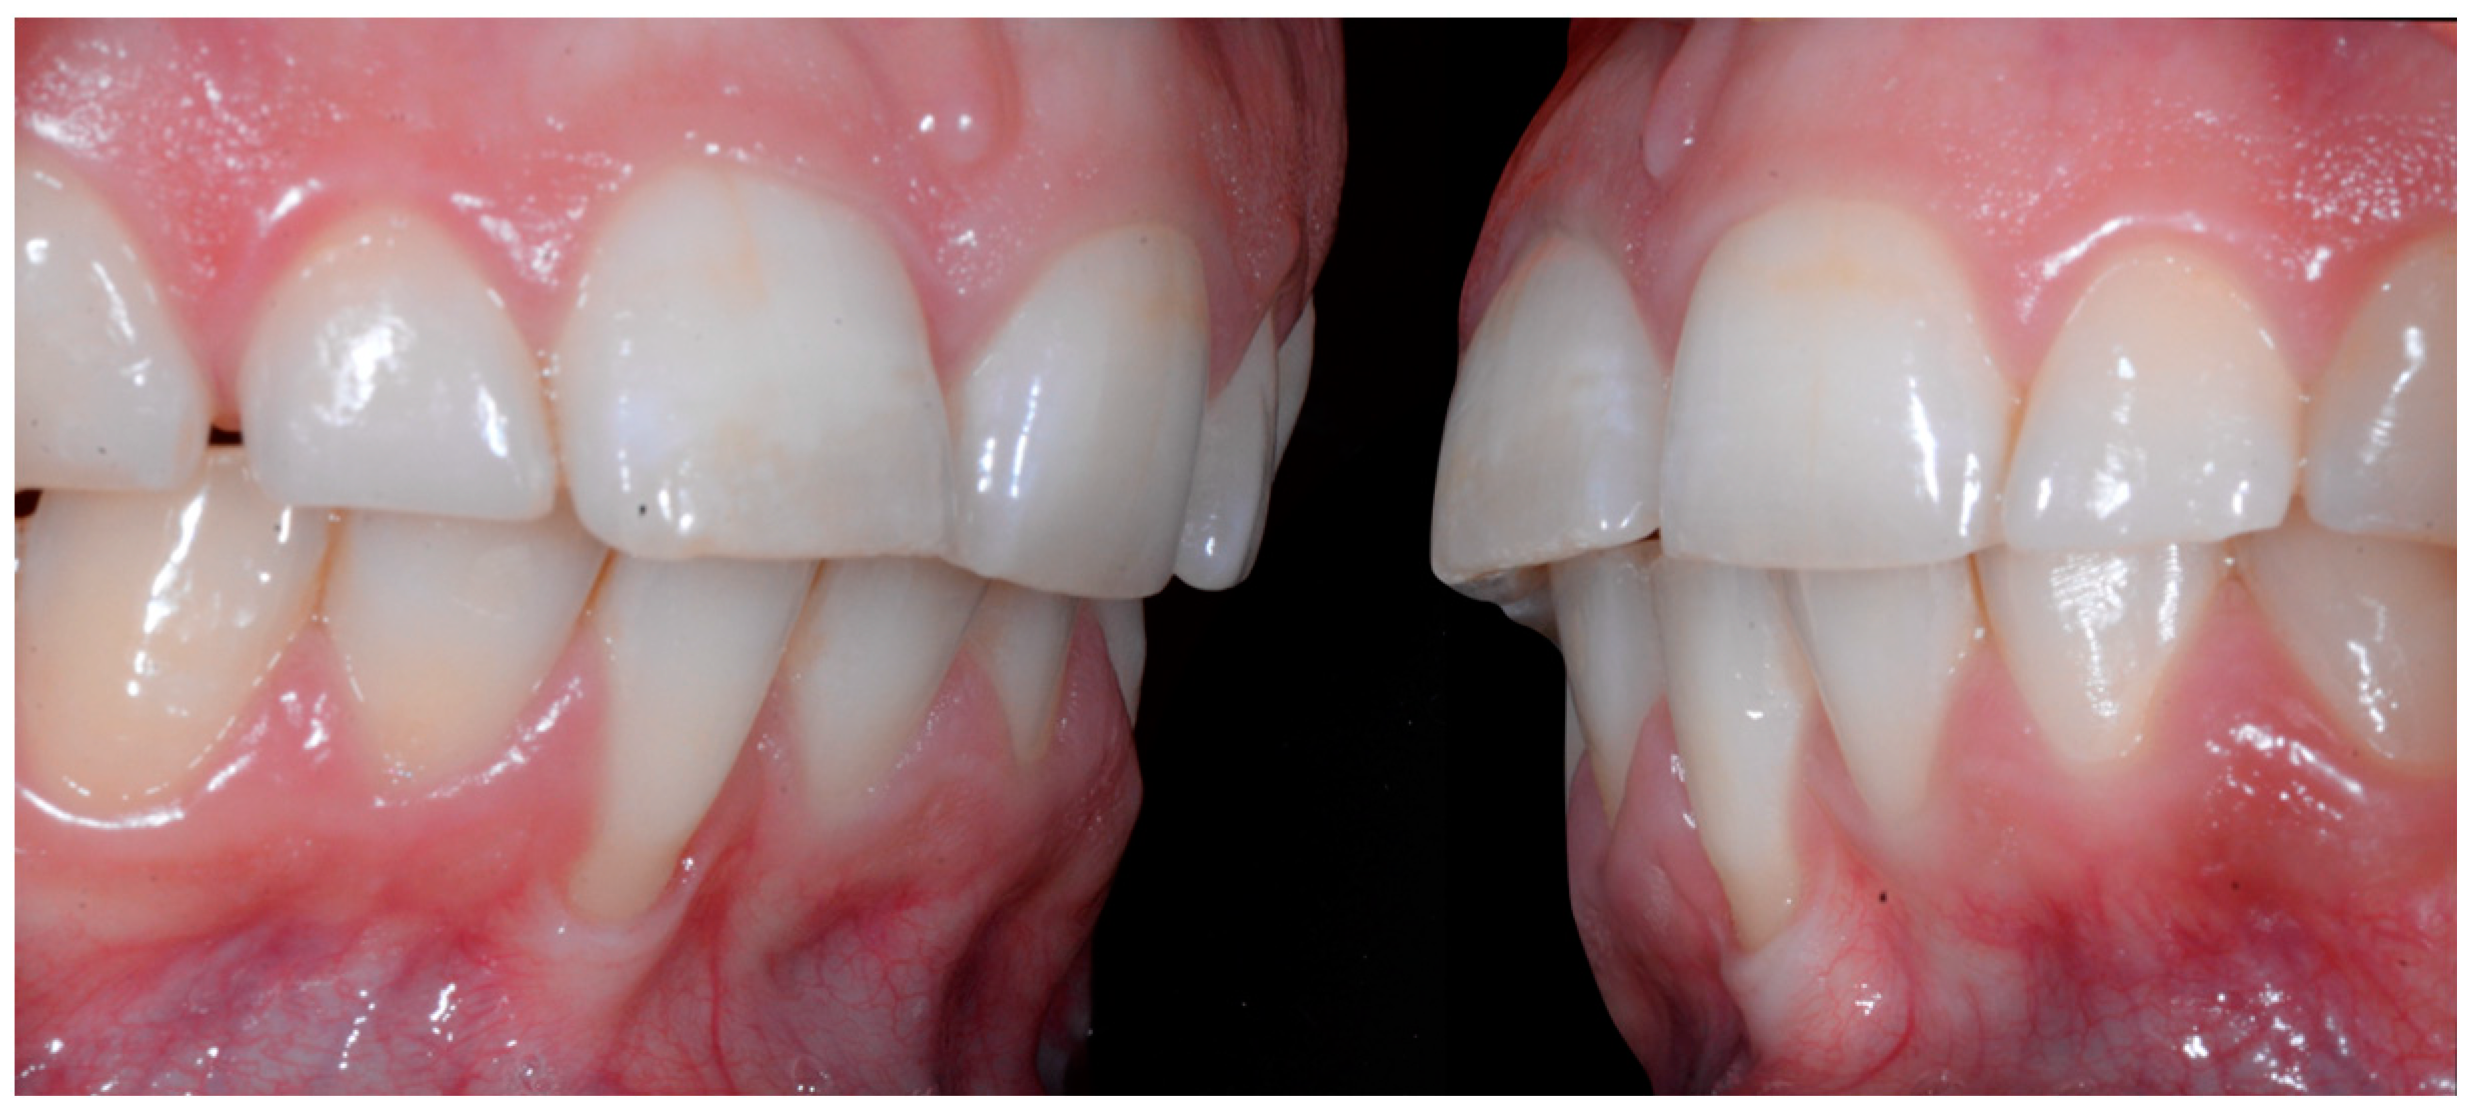

No retainer was present in the maxilla, only a residual mandibular retainer, still bonded to 32 and 42, was visible (Figure 14), as well as incisal crowding and a difference in the visibility of the buccal and root surfaces of 41 compared to the contralaterals. In this extreme clinical situation, a severe and terminal wire syndrome on tooth 41, the “X-effect” type, was observed.

Severe wire syndrome. Occlusal view.